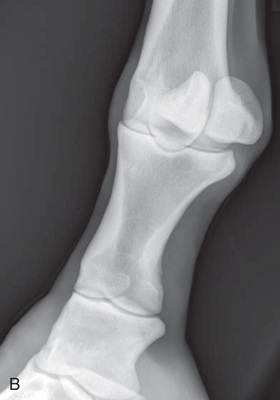

Digit/foot: P-III (distal phalanx, coffin bone) P-II (middle phalanx) P-I (proximal phalanx-pastern) Proximal interphalangeal joint (pastern joint) joint | DP (Standard) (Fig. 24.62B,C) | Dorsal 45-degree proximal–palmarodistal (D45Pr-PaDi) | Foot slightly forward on image receptor. | Perpendicular to foot axis at MSP (midsagittal plane) at area of interest with beam angled ~45 degrees to ground |

| Lateral (Standard) (Fig. 24.62D) | Lateromedial | On a block to elevate limb for P-III; resting on ground for other views. | 90 degrees lateral to MSP, parallel to ground on area of interest: coronary band for PIII | |